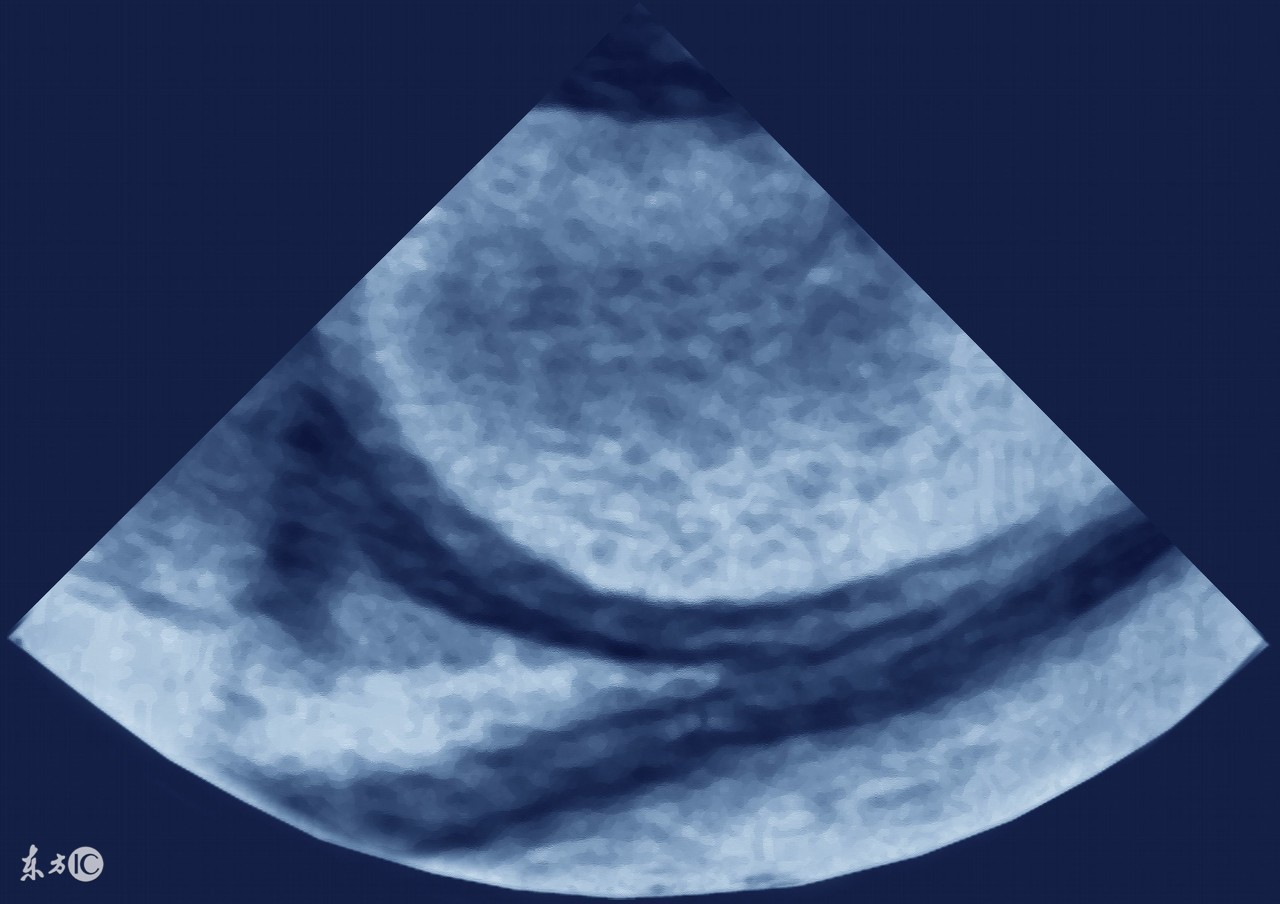

借此机会,就来和大家说一说哪些癌症会引起腹水,因为有不少病人是因为发现肚子鼓鼓的,做B超一看,肚子里有水(腹水),于是找原因,是什么原因引起的腹水?

1、肝癌。前面说了,肝病是引起腹水最常见的原因,其中肝癌就是其一。原发性肝癌,发展到一定程度,合并腹水的可能性非常大,其实本质上仍是肝硬化所致,所以肝腹水就是肝硬化腹水。肝硬化时,肝细胞变性、坏死、纤维组织增生,肝内血管床受压、扭曲、变形、狭窄,阻塞了血管,使肝窦淤血,血流量大大降低,门静脉压力升高,同时,毛细血管静脉压力也升高,久而久之,胃肠道、肠系膜、腹膜等血液回流受阻,血管通透性升高,血液中的血浆成分外漏,形成了腹水。肝功能不合,肝脏不能合成白蛋白,低蛋白血症,由于血清白蛋白的降低,血管内胶体渗透压下降,血浆成分外渗而形成腹水。所以,不管什么肝病,到了肝硬化,肝功能不全的阶段,就可能形成腹水。

3、卵巢癌,包括输卵管癌、原发性腹膜癌,这三种癌症的治疗原则是一样的,这类癌症也是引起腹水的最常见原因之一,女性如果有大量的腹水,要首先排除卵巢癌可能,有针对性的重点查一查卵巢输卵管。